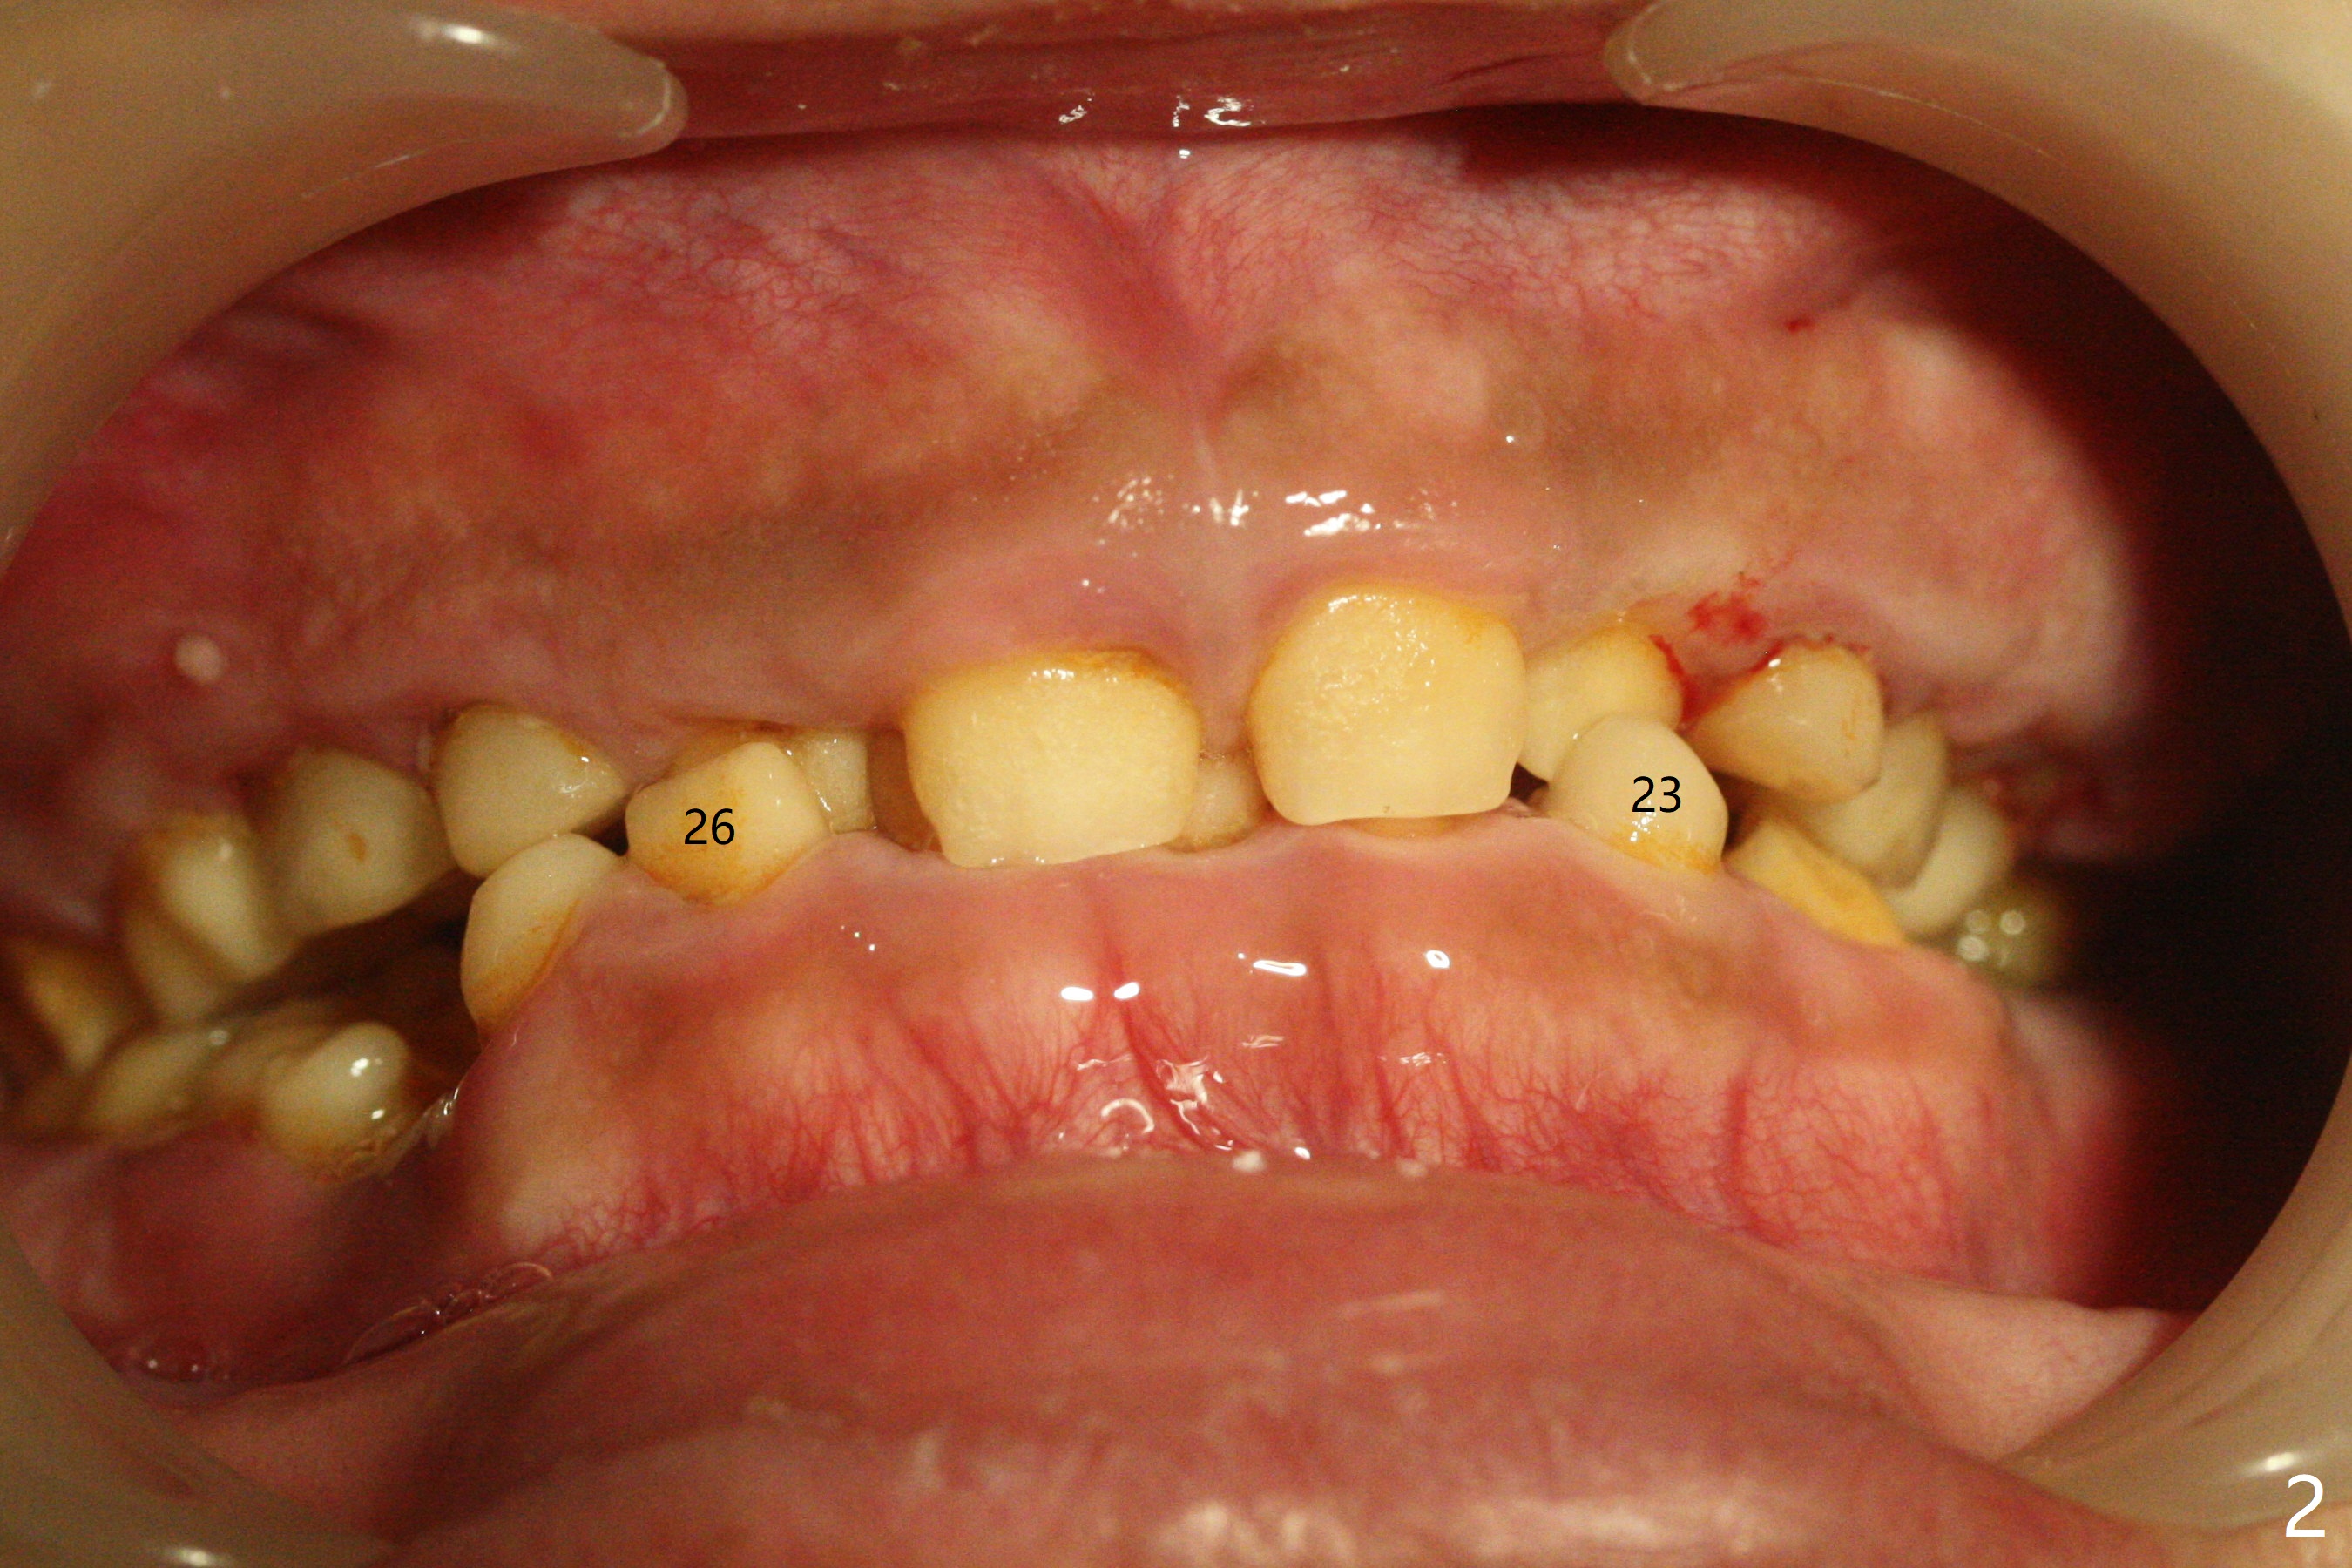

13岁男孩,每颗乳恒牙交换时乳牙都需要拔除,萌出的恒牙个子小,侧切牙反合(图二,五),对冷热敏感,不爱刷牙,口腔卫生欠佳(图三:13(结石)),父母要求诊治。今天在局麻下,左上洁治,没有局麻区域无法洁治,敏感,并且拔除H-J。S下沉,5,28埋伏(图七),其余乳磨牙都有龋齿。如何治疗?是釉质发育不全?暴露5,28前将拍摄CT。